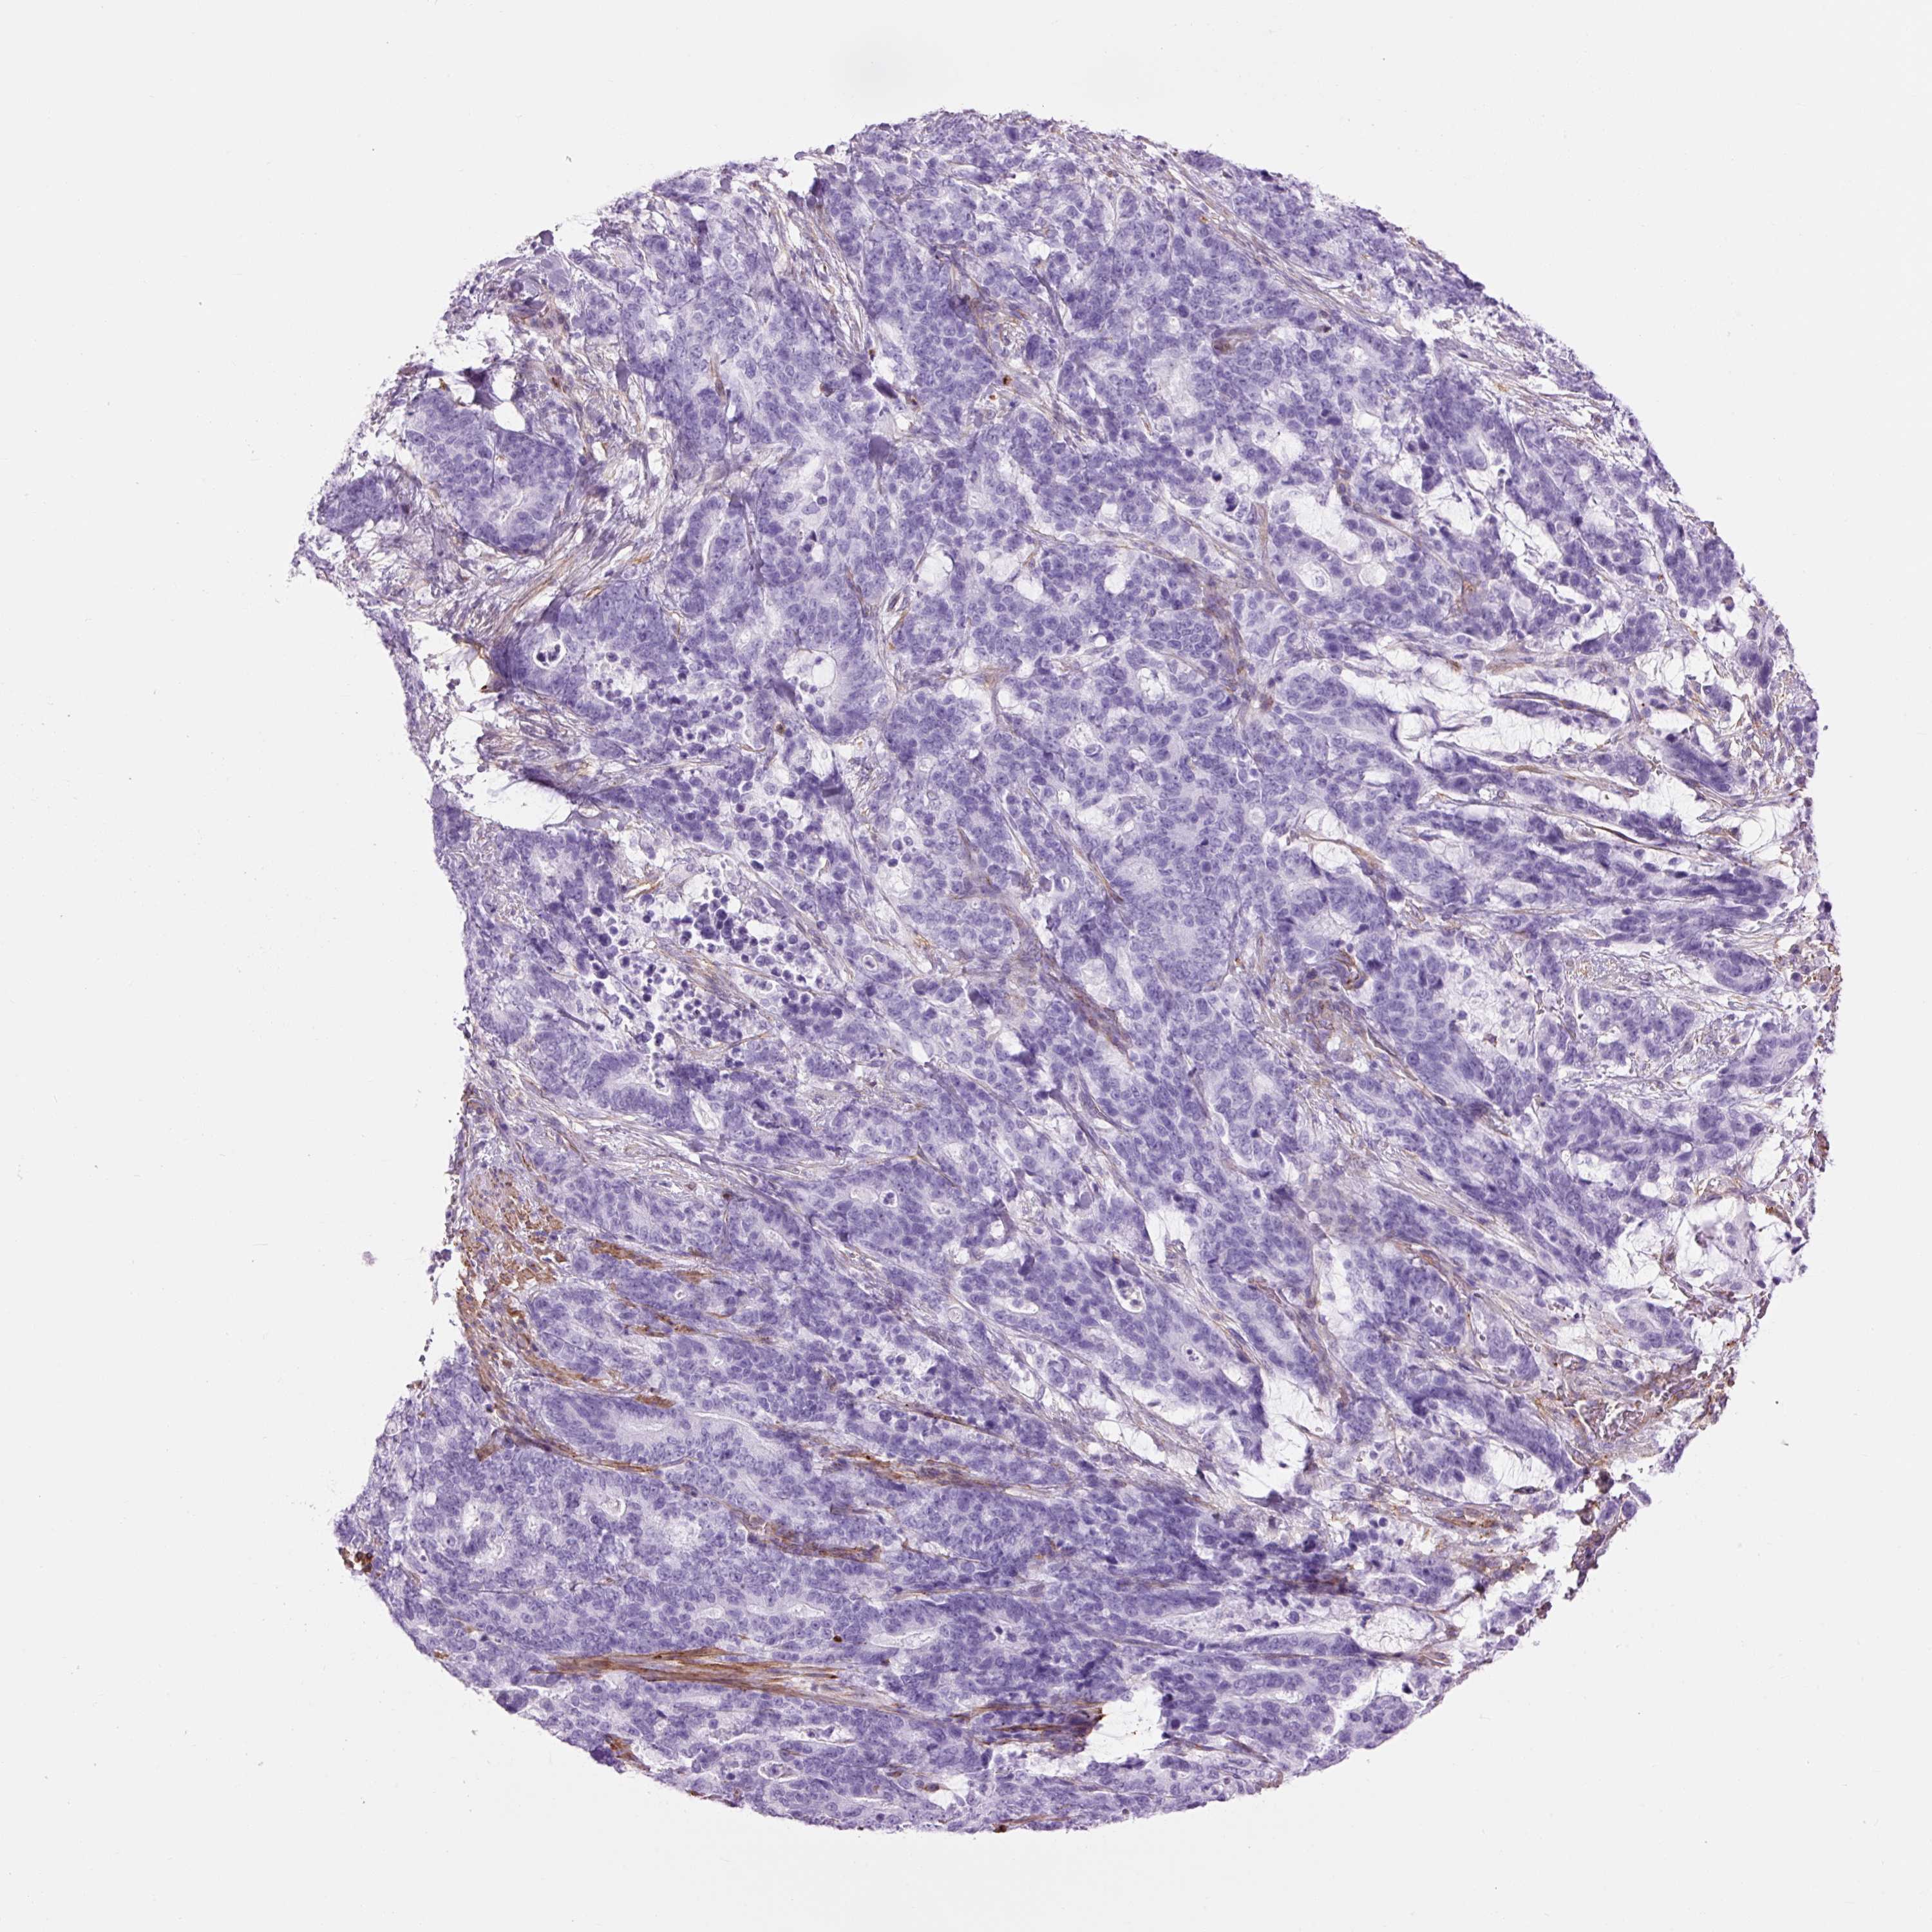

STOMACH CANCER - Protein expressioni

A mouse-over function shows sample information and annotation data. Click on an image to view it in a full screen mode. Samples can be filtered based on level of antibody staining by selecting one or several of the following categories: high, medium, low and not detected. The assay and annotation is described here.

Note that samples used for immunohistochemistry by the Human Protein Atlas do not correspond to samples in the TCGA dataset.

Antibody stainingi

Antibody staining in the annotated cell types in the current human tissue is reported as not detected, low, medium, or high, based on conventional immunohistochemistry profiling in selected tissues. This score is based on the combination of the staining intensity and fraction of stained cells.

Each image is clickable and will lead to virtual microscopy that enables deeper exploration of all samples and also displays staining intensity scores, fraction scores and subcellular localization as well as patient and tissue information for each sample.

Antibody HPA049326

Antibody CAB003791

Staining

High

Medium

Low

Not detected

Intensity

Strong

Moderate

Weak

Negative

Quantity

>75%

75%-25%

<25%

None

Location

Nuclear

Cytoplasmic/membranous

Cytoplasmic/membranous,nuclear

Adenocarcinoma, NOS

Adenocarcinoma, High grade